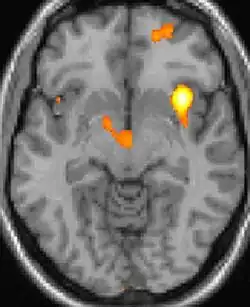

| La tomographie par émission de positons (TEP) montre les zones du cerveau étant activées durant la douleur | ||

Les images par tomographie à émission de positron indiquent les régions du cerveau qui sont activées lors de la douleur, par rapport aux périodes sans douleur. Elles montrent les régions du cerveau qui sont toujours actives durant la douleur en jaune/orange (appelé "matrice-douleur"). La zone au centre (dans les trois vues) est spécifiquement activée uniquement pendant la crise. Les photos sur la ligne du bas (effectuées par VBM) montrent les différences structurelles entre les patients souffrant d'AVF et des personnes saines : seulement une partie de l'hypothalamus est différente[50],[51].